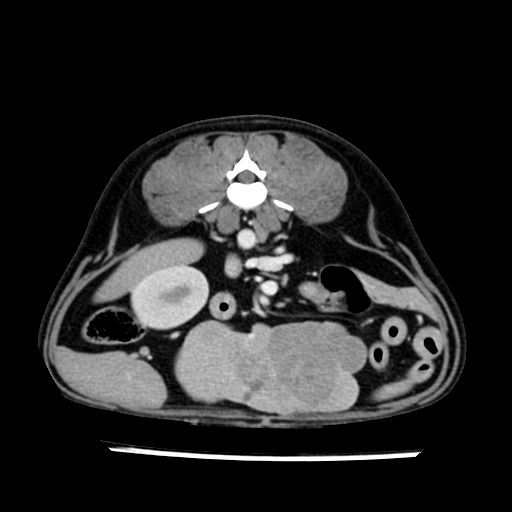

prescritto esame TAC

sequenza immagini limitata al fegato reni e surreni

le immagini ecografiche rispetto alla tac datano circa 7 mesi prima ,le surrenali sono normali nonostante il test acth sia risultato positivo .all’esame TAC dopo diversi mesi risultano aumentate armonicamente nel volume e si individua un forte sospetto di adenoma ipofisario .

sospetto adenoma ipofisario vs. meno probabilmente meningioma della base; intertiziopatia polmonare; lesione espansiva epatica, verosimilmente del lobo laterale sinistro, di sospetta natura neoplastica; lesioni spleniche di natura da definire; iperplasia/ipertrofia delle ghiandole surrenali, bilateralmente; vertebra di transizione del rachide toracico; tenosinovite cronica del muscolo bicipite brachiale di destra.

- Nessuna informazione diversa per quello che riguarda l’esame ecografico del fegato e la presa del contrasto si confermano le lesioni individuate e l’ipoenanchement in fase portale.